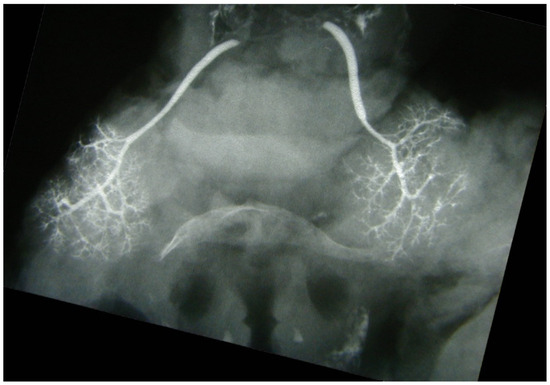

Immediately after injection, the specimens underwent image acquisition on standard radiographic equipment. Their positions in the frontal and the axial planes were controlled beforehand and verified via fluoroscopy (Figure 1 and Figure 2). A metal reference lamina of known width was placed in the vicinity of the specimen, for the purpose of the calibration of dimension, i.e., resolving the magnifying influence of distance between the X-ray tube and the specimen (film). Sialograms were taken under the following parameters: a generator of 42–50 kV and exposure of 3.2–5.0 mAs.

Figure 1. Postmortem sialography of submandibular glands, coronal plane. The ductal arborization is distinct. Hyoid bone is visible in the middle of the image.